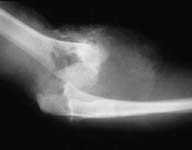

Case 2 - avulsed elbow joint with complete pulling apart of brachial artery, open wound with huge overlying skin loss. Immediate OR, brachial artery shunted, THEN Ortho puts on cross-joint ex-fix, we come back and definitively repair artery (ASVG), document patency with on table completion angio--then plastics swings lat dorsi pedicled flap thru axilla to cover.

Initial xray

Shunt then ex-fix